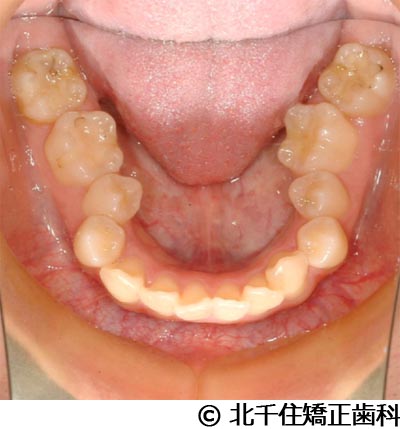

【症例4】下顎前突

- 治療前

- 治療後

- 治療名

- 下顎前突

- 費用

- 1,226,000円(税込)

- 期間

- 2年10ヵ月

- 治療回数

- 32回

- 通院頻度

- 1ヵ月ごと

- 年齢・性別

- 28歳5ヵ月・女性(初診時)

治療内容

患者様の症状

主訴:デコボコ、笑顔のとき歯がきれいに見えるようにしたい

治療方法

骨格性の下顎前突および開咬、上顎第二小臼歯と下顎第一小臼歯4本抜歯してワイヤー矯正(セラミックブラケット)。

治療結果

骨格性下顎前突および開咬に対し、抜歯を併用した矯正治療により歯列および咬合関係の調整を行った症例である。治療後は保定装置を使用し、歯列および咬合の安定維持を目的として定期的な経過観察を行っている。

※治療結果は個人差があります。

治療を行う上での注意点(リスク・副作用)

歯磨き不良に伴うカリエスや歯周病、歯根吸収など。